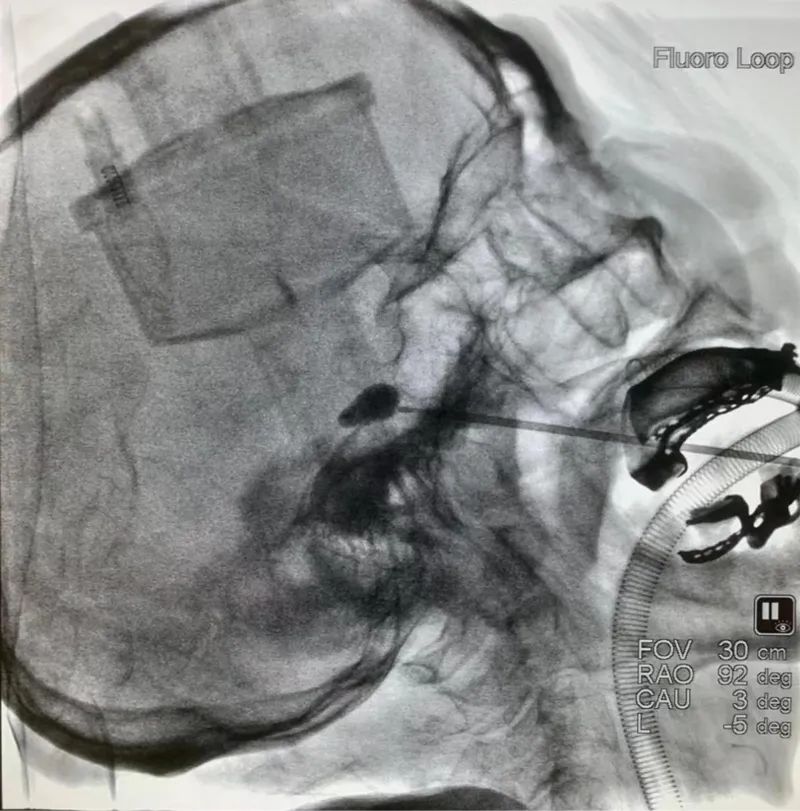

為他在全麻下行

“經皮三叉神經半月節(jié)球囊壓迫術”(PBC)

術中

用一根針

在胡大伯的右側嘴角旁邊

扎一個針眼大小的孔

在介入影像的精準引導下

通過穿刺

將球囊置入到三叉神經半月節(jié)位置

再將造影劑注入球囊中

待球囊擴張呈梨形后

精準壓迫引起疼痛的神經

完成后拔出穿刺針及球囊導管

手術很順利

僅用時20分鐘